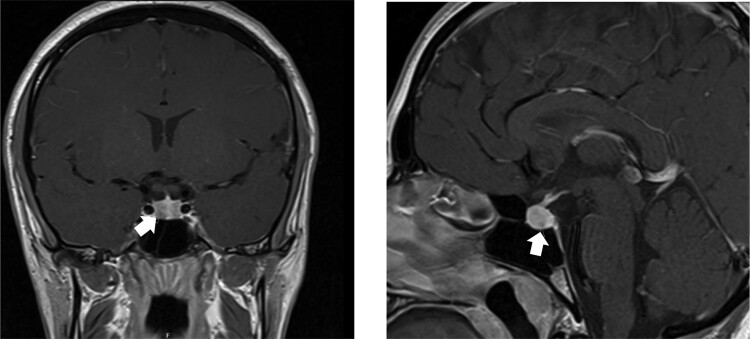

二氢蝶啶还原酶(DHPR)缺乏症是一种阻碍四氢生物蝶呤(BH4)再生的疾病,会导致高苯丙氨酸血症(HPA)和神经递质(包括多巴胺)水平低下。由于多巴胺水平低,患者会出现高泌乳素血症。治疗包括限制苯丙氨酸(Phe)饮食、补充羟色氨酸和左旋多巴(L-Dopa),从而使泌乳素(PRL)水平迅速恢复正常。我们报告了一例 DHPR 缺乏症患者的病例,尽管采取了适当的治疗措施,该患者仍在青春期出现了新的症状性高泌乳素血症和闭经。垂体磁共振成像确认了催乳素瘤。患者开始服用卡贝戈林,PRL 水平迅速恢复正常,症状也得到缓解,这与之前的报道一致。与左旋多巴相比,卡麦角林对D2R受体的亲和力更强,半衰期更长,可导致泌乳素凋亡、肿瘤缩小、PRL水平迅速恢复正常并保持不变,而且副作用更小。由于 L-Dopa 单一疗法不足以抑制 PRL 分泌,导致泌乳素细胞长期肥大和增殖,并在日后发展为催乳素瘤,因此需要积极监测 DHPR 缺乏症患者是否出现症状性高泌乳素血症。

Dihydropteridine reductase (DHPR) deficiency is a disorder that prevents regeneration of tetrahydrobiopterin (BH4), causing hyperphenylalaninemia (HPA) and low levels of neurotransmitters, including dopamine. Due to low levels of dopamine, patients present with hyperprolactinemia. Treatment consists of a phenylalanine (Phe)-restricted diet, hydroxytryptophan and levodopa (L-Dopa) supplementation, leading to a rapid normalization of prolactin (PRL) levels. We report a case of a patient with DHPR deficiency presenting with new symptomatic hyperprolactinemia and amenorrhea in adolescence despite appropriate management. The prolactinoma was confirmed with pituitary magnetic resonance imaging. The patient was started on cabergoline with rapid normalization of PRL levels and resolution of symptoms, in keeping with previous reports. Cabergoline has a stronger affinity for the D2R receptor and longer half-life than L-Dopa, leading to lactotroph apoptosis, tumor shrinkage, and rapid and maintained normalization of PRL levels, with a better side-effect profile. Patients with DHPR deficiency need to be actively monitored for symptomatic hyperprolactinemia, as L-Dopa monotherapy is insufficient to suppress PRL secretion, leading to lactotroph hypertrophy and proliferation over time and development of prolactinomas in later life.